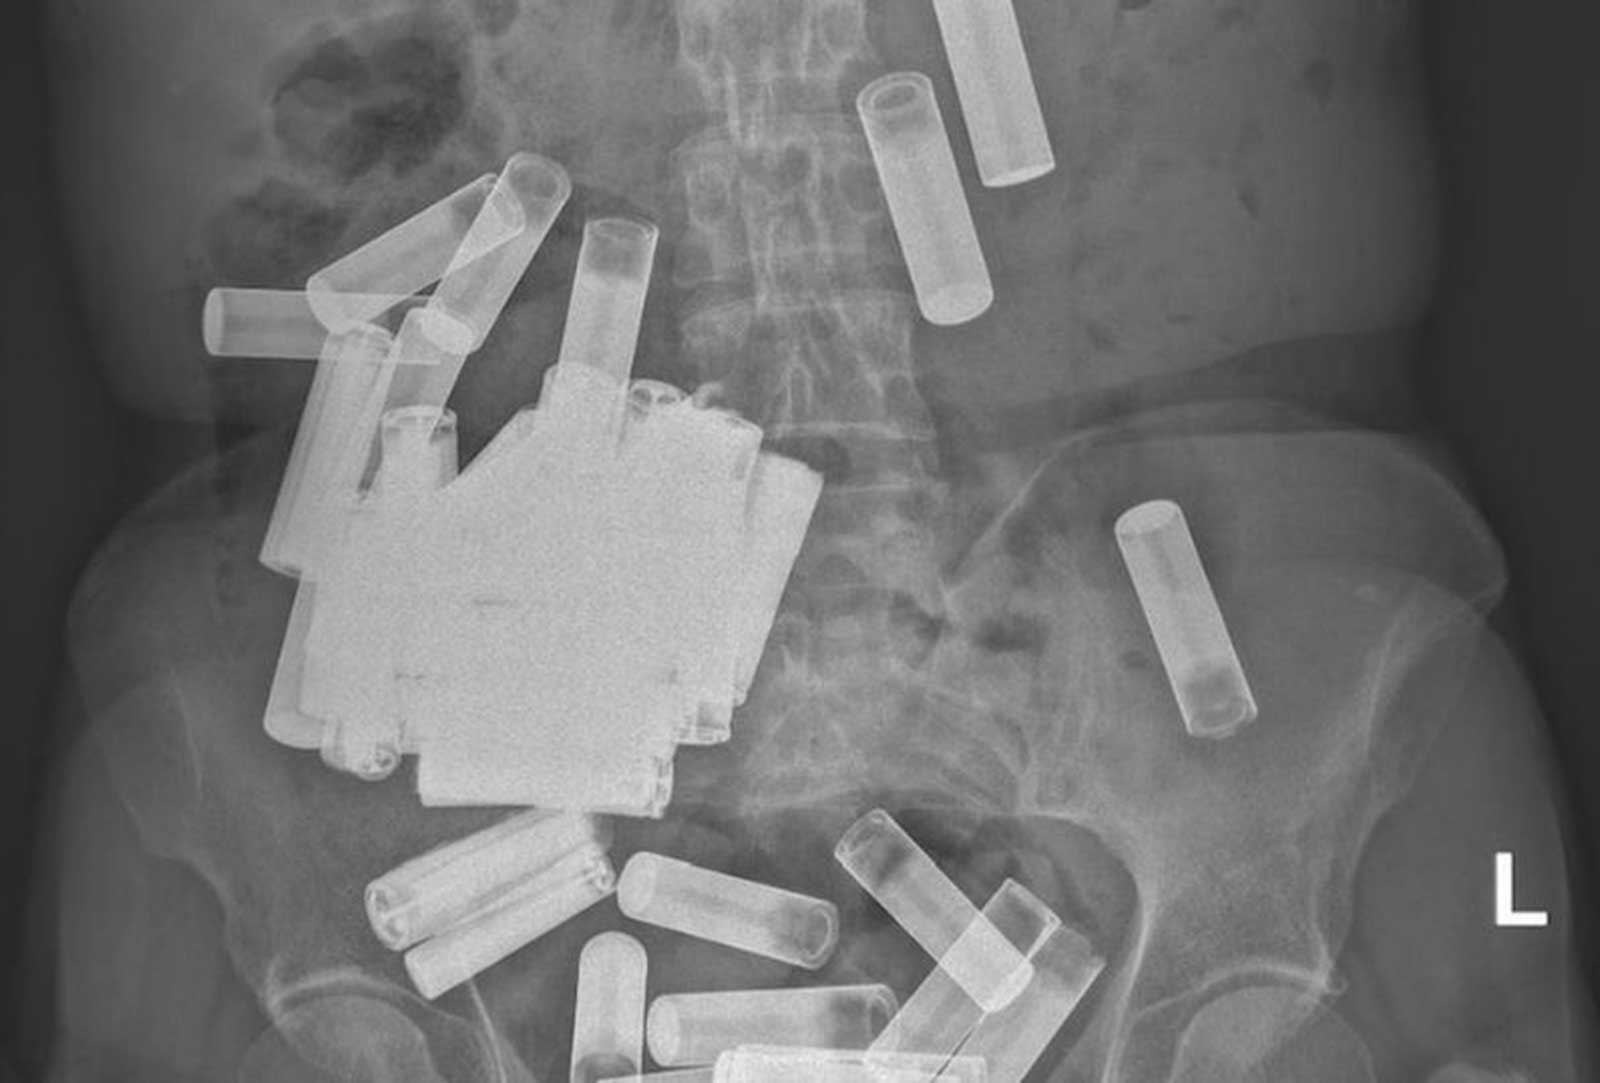

وأوضحوا أنه بمجرد إجراء الأشعة السينية على جسدها تبين وجود 55 بطارية AA وAAA في بطنها وقولونها.

ولفتوا إلى أن المرأة أصيبت بتقلصات في المعدة وانتفاخ بسبب وزن البطاريات التي ابتلعتها.

وأجرى الأطباء للسيدة عملية جراحية لانتشال 46 بطارية، بعدما طرد جسمها 5 بطاريات، وسحبوا 4 أخرى من القولون.